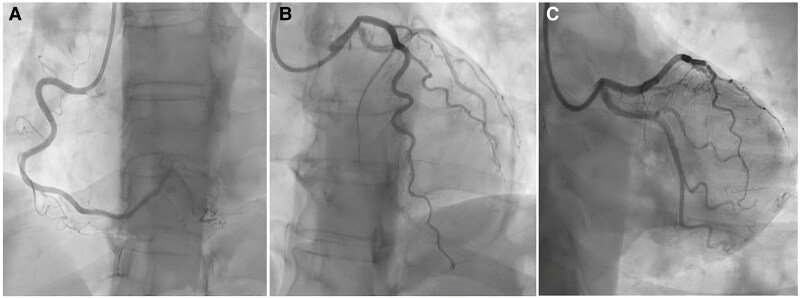

Case summary: A 58-year-old woman with hypertension, prediabetes, and a history of Takotsubo Syndrome presented with recurrent chest pain episodes, prompting multiple ED visits. Initial cardiac evaluations, including electrocardiogram (ECG), troponin levels, and ECG stress testing, were unremarkable. Repeated invasive coronary angiography (ICA) with a full physiological assessment ruled out obstructive CAD, microvascular dysfunction, and coronary vasospasm, suggesting a 'sensitive heart syndrome'. Further evaluation revealed a spinal schwannoma at the thoracic level, compressing the anterior spinal roots. Neuropathic chest pain was confirmed, and treatment with pregabalin led to symptom relief.